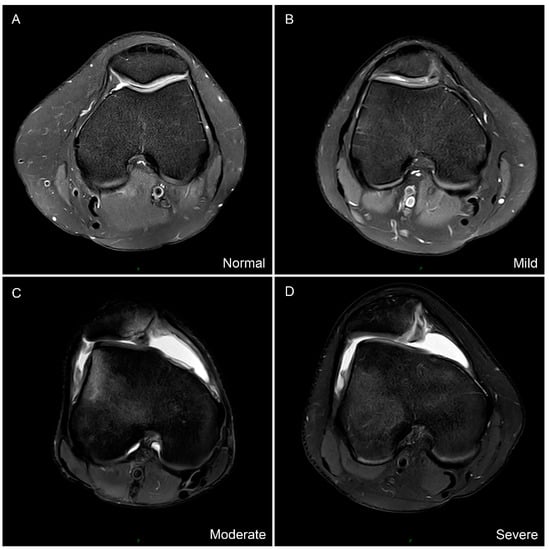

| Trochlear dysplasia (Normal/Mild/Moderate/Severe) | 4/24/20/38 | 84/2/0/0 | <0.001 a |